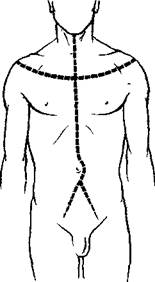

По методу Абрикосова

Рекомендуется делать разрезы с каждой стороны шеи от сосцевидных отростков до рукоятки грудины, Отсепа-рованный до нижней челюсти треугольный кожный лоскут отбрасывают на лицо трупа, и органы шеи широко открываются.

Для детального исследования надключичных, подмышечных и паховых областей А. И. Абрикосов рекомендует комбинированный разрез (рис. 30). При этом разрез пo средней линии ниже пупка разделяют на два разреза, идущие в паховые области, и делают поперечно-полукружный разрез через грудную клетку по методу Лешке.